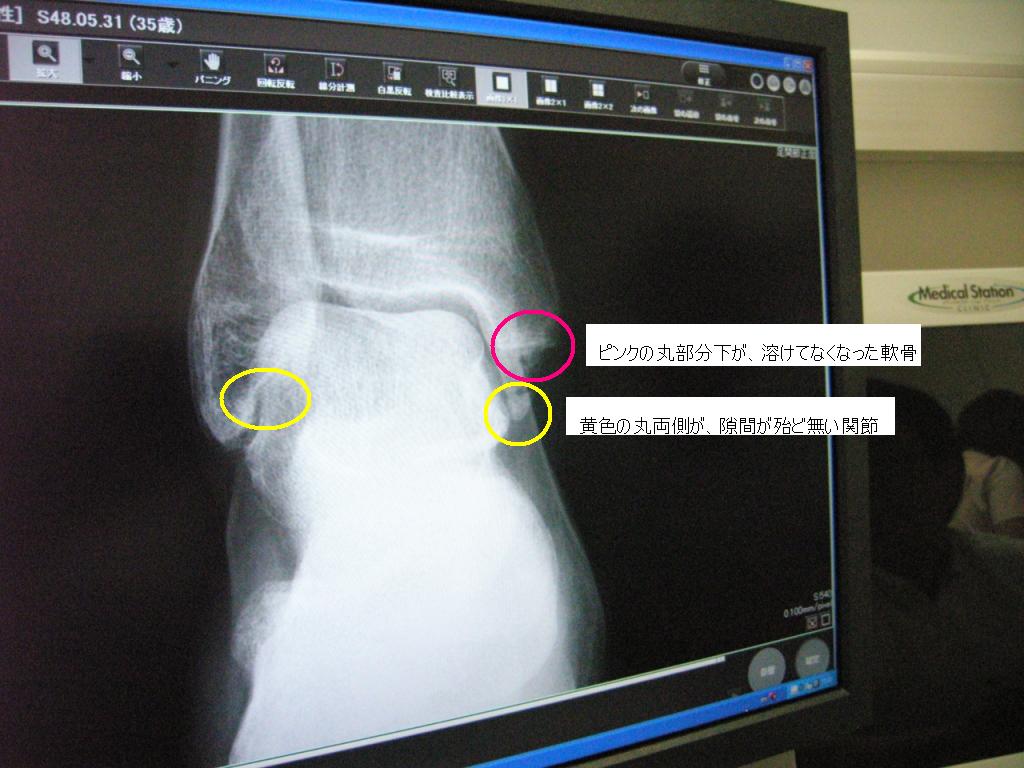

◆無くなった郷の軟骨っ♪

先生様『ほらここ、右足首クルブシの下スッポリ溶けてるね』

ショックに追い討ちをかけるように、足首の左右にある間接の隙間が殆んど無い状態であることを告げられる。

写真のとおりじゃ♪

ピンクの丸で囲んだところを見てクリリン

真一文字(横線)の下にほんらいは三角形の軟骨があるのじゃが、段のようになり、すっぽり無くなってしまってるのよ♪

郷吉ショックじゃった。あぃ